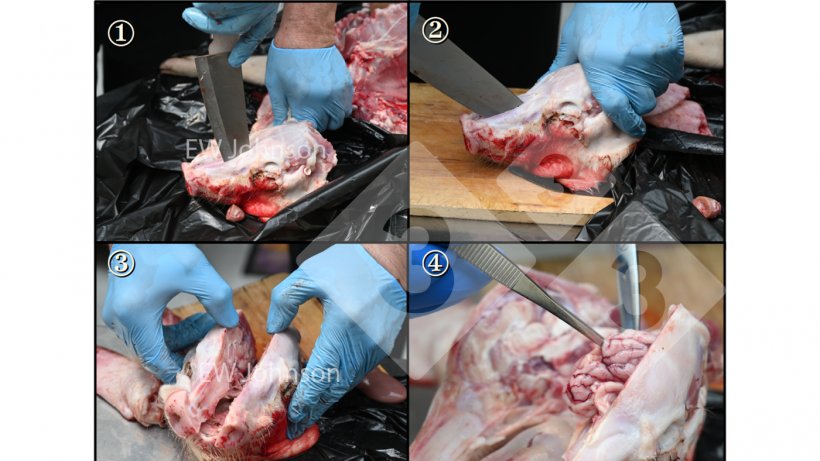

Fot. 2. Aby uniknąć zakażenia krzyżowego podczas pobierania próbek z mózgu, należy przestrzegać ściśle określonych zasad podczas sekcji zwłok i używać sterylizowanego płomieniowo (i chłodzonego) mocnego noża do otwierania czaszki oraz płomieniowanych i chłodzonych kleszczy/nożyc do wyjmowania mózgu.

Pobieranie próbek: Każda próbka musi być umieszczona w osobnym worku, aby uniknąć zanieczyszczenia krzyżowego. Próbki należy pobierać z zachowaniem ostrożności, a do opalania narzędzi należy używać alkoholu i zapalniczki.

- najpierw otwórz klatkę piersiową, aby mieć pewność, że płuca nie zostaną zanieczyszczone

- następnie mózg

- a następnie jelita, i to w takiej kolejności.

Jeśli najpierw zbadasz jelita, to to, co jest w jelitach, znajdziesz we wszystkich innych tkankach.